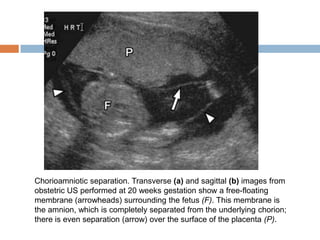

Chorioamniotic separation

   The placental and fetal membranes (chorion and

amnion, respectively) are separate early in

gestation, accounting for the appearance of the

amniotic sac. After approximately 14 weeks

gestation, these membranes fuse and are no

longer separately distinguishable (12).

   In rare cases, chorioamniotic separation can

occur later in gestation. This can be focal or

extensive, with the amniotic membrane becoming

either free floating or adherent to the fetus.

Extensive cases pose a risk to the fetus, with

increased rates of both preterm delivery and the

development of amniotic bands (12).

   Chorioamniotic separation is most commonly

related to prior intervention such as

amniocentesis or surgery but can occur

sporadically. Sporadic cases have been

associated with increased rates of underlying

fetal chromosomal and developmental

abnormalities

   Chorioamniotic separation is usually detected

with US and is visible as a free-floating or

adherent membrane surrounding the fetus.

Separation can extend throughout the entire

uterine cavity and over the surface of the

placenta.

Chorioamniotic separation. Transverse (a) and sagittal (b) images from

obstetric US performed at 20 weeks gestation show a free-floating

membrane (arrowheads) surrounding the fetus (F). This membrane is

the amnion, which is completely separated from the underlying chorion;

there is even separation (arrow) over the surface of the placenta (P).

Chorioamniotic separation  The placental and fetal membranes (chorion and amnion, respectively) are separate early in gestation, accounting for the appearance of the amniotic sac. After approximately 14 weeks gestation, these membranes fuse and are no longer separately distinguishable (12).  In rare cases, chorioamniotic separation can occur later in gestation. This can be focal or extensive, with the amniotic membrane becoming either free floating or adherent to the fetus. Extensive cases pose a risk to the fetus, with increased rates of both preterm delivery and the development of amniotic bands (12).

Chorioamniotic separation is most commonly related to prior intervention such as amniocentesis or surgery but can occur sporadically. Sporadic cases have been associated with increased rates of underlying fetal chromosomal and developmental abnormalities

Chorioamniotic separation is usually detected with US and is visible as a free-floating or adherent membrane surrounding the fetus. Separation can extend throughout the entire uterine cavity and over the surface of the placenta.

Chorioamniotic separation. Transverse(a) and sagittal (b) images from obstetric US performed at 20 weeks gestation show a free-floating membrane (arrowheads) surrounding the fetus (F). This membrane is the amnion, which is completely separated from the underlying chorion; there is even separation (arrow) over the surface of the placenta (P).